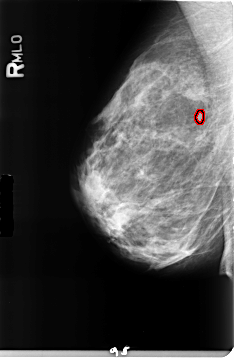

B_3157_1.RIGHT_MLO

RIGHT_MLO LINES 4672 PIXELS_PER_LINE 3032 BITS_PER_PIXEL 12 RESOLUTION 50 OVERLAY

FILE: B_3157_1.RIGHT_MLO.OVERLAY

TOTAL_ABNORMALITIES 1

ABNORMALITY 1

LESION_TYPE MASS SHAPE LOBULATED MARGINS CIRCUMSCRIBED

ASSESSMENT 4

SUBTLETY 4

PATHOLOGY BENIGN

TOTAL_OUTLINES 1

BOUNDARY